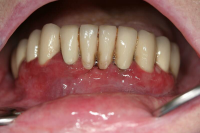

En volymökning av mjukvävnaden kring tänderna som är associerad med intag av läkemedel tillhörande grupperna antiepileptika, immunosuppressiva läkemedel och kalciumblockerare.

Inflammation är den utlösande faktorn som driver tillväxten av mjukvävnaden därför är plackkontroll av största vikt.

Diagnostik

Förekomst av gingivala hyperplasier med djupa tandköttsfickor och svåra hygienförhållanden som följd.

Läkemedelsinducerad gingival hyperplasi: